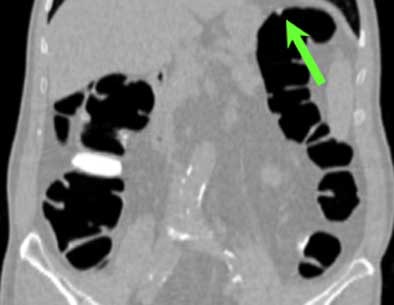

| Top to bottom: A 10-mm polyp in the splenic flexure can be seen in axial, sagittal, coronal, and 3D views. All images courtesy of Dr. Riccardo Iannaccone, University of Rome "La Sapienza." |

Per patient, virtual colonoscopy yielded an average sensitivity of 89.9% (95% CI, 90.9%-96%), average positive predictive value of 88% (95% CI, 83.3%-91.5%), and average negative predictive value of 93.5% (95% CI, 90.9%-96%), the authors wrote. In the more rigorous per-polyp analysis, VC's overall sensitivity was 64.4% (95% CI, 60.2%-68.7%; 72% for neoplastic polyps), including 95.5% sensitivity for polyps ≥ 8 mm (95% CI 92.1%-99%; 100% for neoplastic polyps), and 86% for polyps ≥ 6 mm (95% CI, 81.7%-90.5%).

Virtual colonoscopy produced 16, 16, and 21 false-positives for each of three readers, most due to the presence of thickened folds, and surprisingly in the prep-free study, few false-positives (4, 4, and 5, respectively) were due to fecal material. "This result is correlated to the fact that the use of an effective fecal tagging strategy in our study helped the readers in the differentiation between fecal material and colonic polyps," the authors wrote.

There were also 54, 57, and 52 false-negatives at VC, with no clear cause determined for 59, 51, and 53 of them, even in retrospective analysis. These may have been due to the limits of spatial resolution in the image data, but most of the lesions carried a very low likelihood of malignancy, the group noted. Interobserver agreement between the three readers was high both per-polyp (k = 0.61-0.64) and per patient (k = 0.79-0.91).